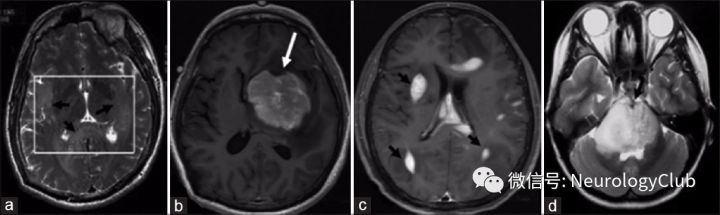

平扫时多数TDLs病灶呈低密度(图2a),少数为等密度(图3b),增强扫描时强化不明显。

1. MRI平扫:TDLs病灶常为T1WI低信号,T2WI高信号,较CT显示的病灶范围大。约70-100%TDLs患者的病灶在T2WI上为高信号,边界清楚(图5b),而少数病灶的边缘可见T2WI低信号(图4a)。大多数TDLs病灶具有占位效应(图1a,2b,2c,和3a),但较脑肿瘤轻,病灶周围常可见水肿。在急性或亚急性期,水肿主要为细胞毒性水肿,DWI序列上为高信号(图4b)。经激素治疗后,病灶可在数周内变小或消失。

2. 增强MRI:在急性期或亚急性期,由于血脑屏障的破坏,增强MRI可见不同模式的强化,如结节状、闭环、开环或火焰状强化。开环强化又称为C形强化(图5a),是最典型的,即病灶边缘不连续的半环形强化。对于部分TDLs病灶,扩张的小静脉形成梳齿状结构(图1b和2d),垂直于侧脑室,常见于急性期或亚急性期,是TDLs相对特异的影像表现,而未见于脑肿瘤。

图2:轴位CT上的TDLs病灶:双侧半卵圆区大片状低密度灶(a);FLAIR序列:右侧半卵圆区大片状高信号影,左侧半卵圆区多发斑片状高信号影(b);T2WI:右侧半球大片状高信号影(c);T1增强:梳齿状强化,垂直于侧脑室(d

图3:轴位MRI FLAIR上可见蝴蝶状的TDLs病灶(a);轴位CT上同样的病灶表现为大片状稍低密度影(b);胼胝体III级星形胶质细胞瘤,胼胝体压部和双侧顶枕叶之间可见大片弥漫稍高密度影(c);PCNSL患者(弥漫性大B细胞淋巴瘤)轴位CT可见左侧基底节区“肾”形高密度病灶(d